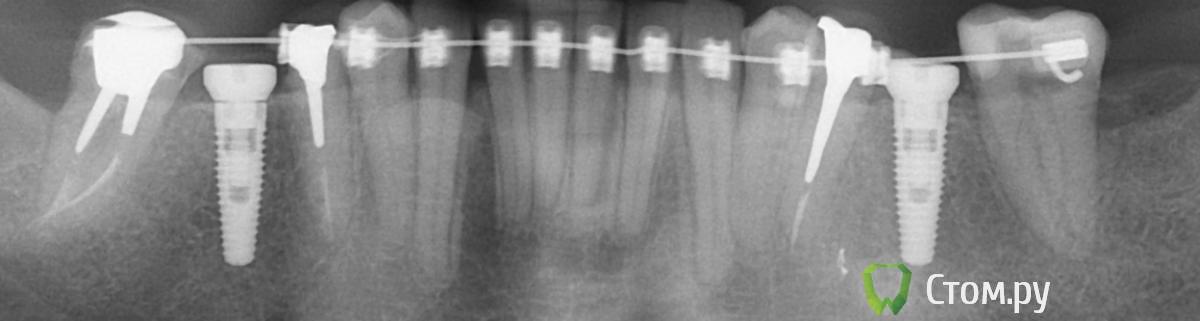

doctore Опубликовано 17 ноября, 2011 Автор Поделиться Опубликовано 17 ноября, 2011 (изменено) Как пример -33/34/35/ или 44/45.Прицельные снимки подтверждают . Изменено 17 ноября, 2011 пользователем doctore Ссылка на комментарий

Премоляр Опубликовано 17 ноября, 2011 Поделиться Опубликовано 17 ноября, 2011 Да уж,доктор, "притирание корней"-это круто (п.с. универ давно закончили???)По теме- вследствие неправильно зафиксированных брекетов чаще всего бывает конвергенция или дивергенция корней,тоесть их нефизиологичное положение..Отсюда и рецидив,и осложнения и т.д...Методам устронения этого учат в ординатуре(перепозиционирование брекетов, изгибы на дугах...).Перед снятием бректов необходимо изменить положение корней.П.С. Слава богу что к имплантам "притирания" не возникло Ссылка на комментарий

Премоляр Опубликовано 17 ноября, 2011 Поделиться Опубликовано 17 ноября, 2011 Коллеги, поделитесь тактикой лечения при ситуации притирания корней.Оставляете так или нет.Прогноз при снятии брекетов с притершимися корнями.Что именно в процессе лечения приводит к неконтролируемому перемещению, и как следствие ,притиранию?Еще раз отвечу-1- "Коллеги, поделитесь тактикой лечения при ситуации притирания корней".- Если такая ситуация возникла,необходимо изменить положение корней путем перепозиционирования брекетов или изгибами на дугах2- " Оставляете так или нет" -нет3- ".Прогноз при снятии брекетов с притершимися корнями" -рецидив4- ."Что именно в процессе лечения приводит к неконтролируемому перемещению, и как следствие ,притиранию? "-именно неконтролируемое перемещение и приводит. Перемещение зубов должно быть контролируемым.Неконтролируемое перемещение-это вторичные окклюзионные деформации,возникающие постепенно после удаления зубов. А ортодонтическое лечение-это контролируемое перемещение зубов.Кратко попытался прояснить...Если точнее-то конкретизируйте вопросы Ссылка на комментарий